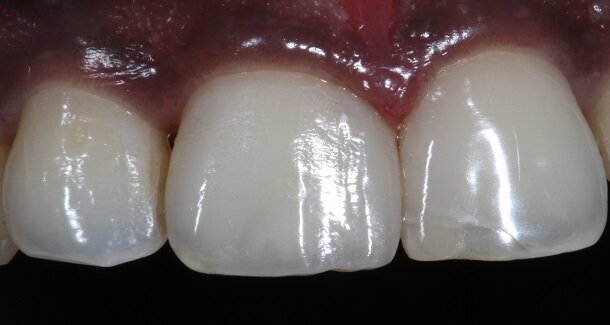

The figures show the clinical work flow involved. In the 1st appointment Oral prophylaxis, oral hygiene instructions were followed by an impression that was sent to the lab for a wax up [Fig 3 and 4]. In the subsequent appointments, Endodontic treatment was followed by Intra and extra coronal office bleaching using the Pola office bleaching kit. After two weeks, the shade stabilised post bleaching. Shade selection, rubber dam isolation and preparation was done on both the teeth to receive Direct composite veneers so as to close the midline diastema as well as correct the fractured teeth and the slight mal-alignment. Controlled Body Thickness (CBT) technique of layering was used with 3M Z350XT shades - Dentin shades A3, A2 and Enamel shades A2, clear translucent [Figures 5 to 11]. This was followed by the Finishing and polishing protocol as described in the figures.

Characterisation begins during Dentin Layering itself. [Fig 9] Shape of the tooth is extremely important. A well-made putty key from a wax-up or a mock-up can help in maintaining shape of the tooth. [Fig 3 and 4]